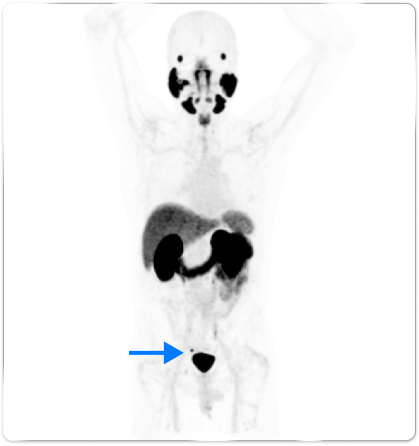

Patient A

Anterior whole body PYLARIFY PET MIP showed uptake in the right peri-rectal lymph node (blue arrow)

In patients with similar profiles, PYLARIFY identified differences in extent of disease, guiding treatment changes

- Treatment change from EBRT to pelvis with additional boost to prostatic fossa, to lesion-specific SBRT

- Post-treatment PSA levels dropped to 0.06 ng/mL